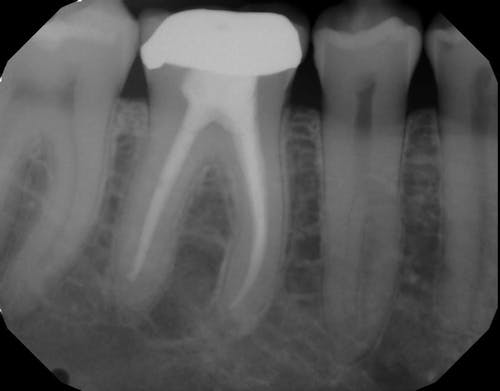

So, what is a root canal? When a damaged, chipped or diseased tooth—or teeth—causes pain, discomfort, or sensitivity, which cannot be reversed by other means, a root canal is often the best treatment. Essentially, a root canal removes and deactivates the nerve endings—or pain receptors—reversing your ability to feel pain in those teeth. This process saves your natural tooth while eradicating the pain.